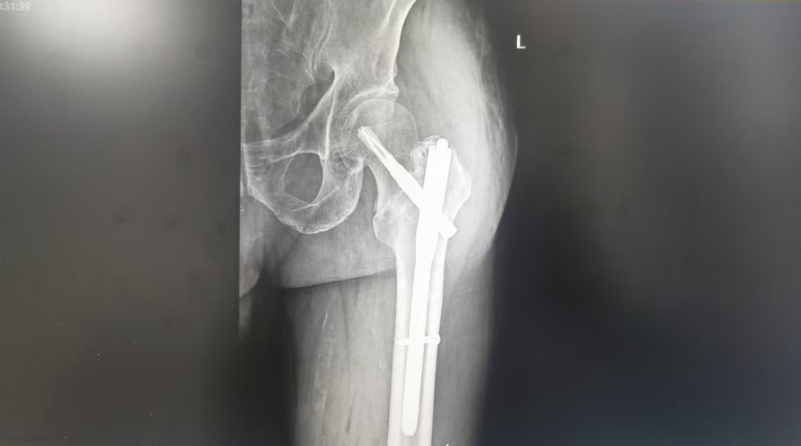

在住院期间,根据患者的病史及检查结果,结合患者的基础疾病,在征得患者及其家属的同意后,按照手术方案,快速完善术前相关检查和术前评估,并拟定详细的治疗方案和各种并发症预案后。由十二团医院外科主任高喜成主刀,在麻醉科、手术室护士等外科医护团队在术中密切配合下,高喜成凭借丰富的手术经验和精湛的技巧,在十二团医院成功完成首例高龄患者股骨转子间骨折闭合复位内固定术,患者从入院到手术仅用了3个小时,标志着医院创伤骨科的救治水平得到了进一步提升。

高喜成主任表示,股骨转子间骨折多数与骨质疏松有关,最常见于老年人,以前因多重原因无法手术,患者因此骨折而死亡的发生率高,被誉为“人生最后的骨折”。因此,老人们在生活中一定要注意安全,避免摔伤、跌倒。股骨转子间骨折属于大关节周围的骨折,一旦骨折会严重影响患者的活动及生活质量,同时,符合手术适应症的患者,应尽早接受手术治疗,才能获得最佳恢复效果。